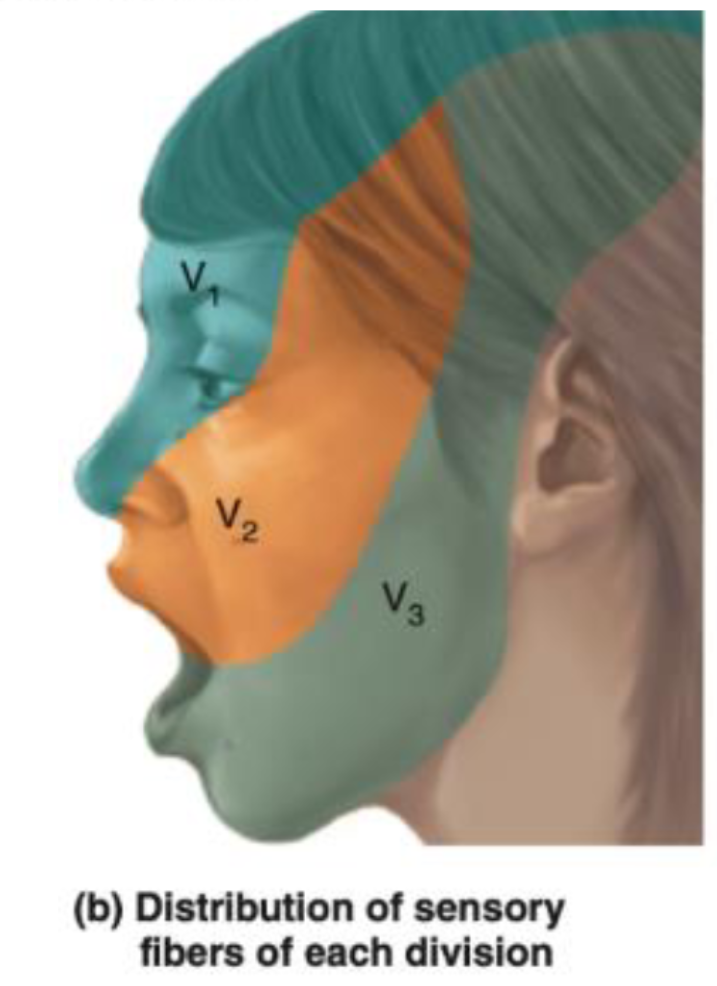

⑤: Sensory, Pain, Temp, Motor, Masticatication, jaw reflex

- Trigeminal Nerve CN V; light touch sensation, Clench teeth - observe masseter/Temporalis, Jaw Jerk

CN V – Trigeminal Nerve

Ophthalmic (V1) - Passes through the superior orbital fissure.

- Supplies: Sensation to the forehead, upper eyelid, and cornea.

- Involved in the corneal reflex: The afferent limb (sensory input) of the corneal reflex is through the ophthalmic branch of the trigeminal nerve. The efferent limb (motor output, which closes the eye) is via the facial nerve (CN VII).

Maxillary (V2) - Passes through the foramen rotundum.

- Supplies: Sensation to the middle part of the face, cheek, upper lip, and upper teeth.

Mandibular (V3) - Passes through the foramen ovale.

- Supplies: Sensation to the lower part of the face, lower lip, and lower teeth. It also carries motor fibers to the muscles of mastication.

- The anterior two-thirds of the tongue receives general sensation (not taste) via the lingual nerve, a branch of the mandibular division.

- Taste from the anterior two-thirds of the tongue is carried by the chorda tympani nerve (a branch of the facial nerve, CN VII), not the trigeminal nerve.

Sensory Testing:

- Cotton Test: Use a soft piece of cotton to lightly touch different areas of the face. This tests the sensory function of all three branches of the trigeminal nerve. The patient should have their eyes closed during the test to rely solely on their sensory perception. Specifically, test:

- The forehead, upper eyelids, and cornea (ophthalmic branch).

- The cheeks, upper jaw, and upper teeth (maxillary branch).

- The lower jaw, lower teeth, and part of the tongue for general sensation (mandibular branch).